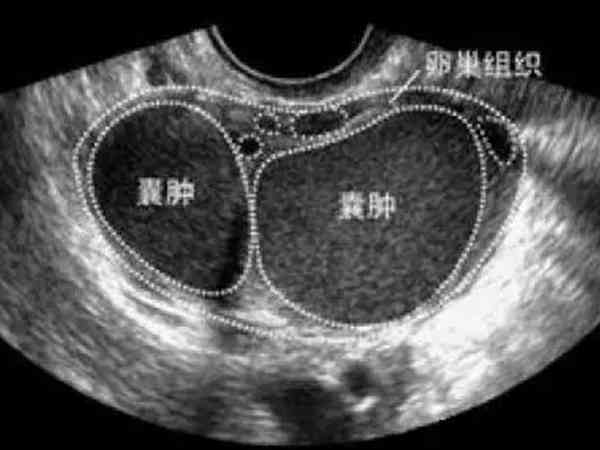

巧克力囊肿实际上就是子宫内膜异位症的一种,当检查到有子宫内膜异位症时,那么就需要及时的进行治疗,否则对身体会造成危害,并且想怀孕的话也就困难。至于巧克力囊肿做试管是否会有影响,又能否促排卵,在文中就能知晓详情。巧克力囊肿是由于内膜异位症引起的巧克力囊肿是由于异位的子宫内膜在卵巢内生长,随着月经周期而出血,形成存在陈旧性积血的囊肿。囊肿内容物通常呈咖啡色,黏稠如糊状,像巧克力样,因此俗称“卵巢巧克力...

双侧巧克力囊肿手术存在一定的潜在危害,特别是卵巢储备功能损害,而试管婴儿着床成功率主要取决于卵巢储备功能、精子质量、子宫内膜环境等因素,所以双侧巧克力囊肿手术后做试管的成功率高不高并不确定,需要由生殖医生评估一下卵巢功能、男方精液质量以及子宫内膜情况后才能知晓。巧克力囊肿是子宫内膜异位症的一种病理改变,可以发生在身体的各个部位,几乎无所不在,最常发生在卵巢,其次是子宫周期的组织。对于有生育要求的双...